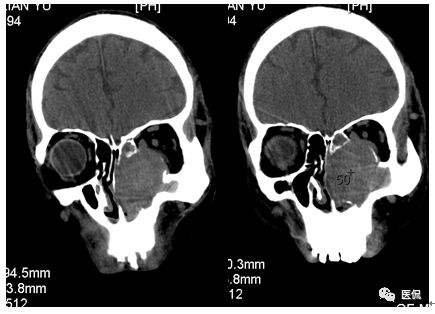

增强动脉期

增强静脉期

CT平扫及增强示:左侧上颌窦及鼻腔可见软组织密度影,呈膨胀性生长,周围骨质压迫性吸收破坏,累及左眶,病灶密度不均匀,周边区可见点状钙化,增动脉期轻度强化,局部见小灶性稍高密度区,静脉期病灶内见不均匀明显强化,CT值最高达117HU,延迟期强化范围有所增大。

影像学表现呈软组织密度,多不均匀,表现为高低混杂密度,病变窦腔内息肉、血肿、坏死、感染共存,是病灶密度不均匀的主要原因,息肉反复出血、血管机化亦为其成因之一。病灶内钙化,可为团块状或小片状,可能为病变组织坏死后钙质沉着所致。由于病变组织内有大量炎性细胞浸润和丰富的毛细血管,增强后常有强化。有文献报道病灶增强中心区强化不明显,外周呈轻度强化,推测病灶内虽然血管丰富,但中心区容易出现血流动力学障碍,血管内常有血栓形成,中心区易发生出血坏死,另外,可能与增强扫描延迟时间选择不当有关。

本例病灶较大,周围骨质可见吸收破坏,并累及眼眶,病灶内少量钙化,增强扫描具有一定特征性,表现为动脉期轻度强化,局部见小灶性稍高密度区,静脉期病灶局部呈明显强化,CT值最高达117HU,延迟期强化范围有所增大,呈延迟渐进性强化的特点,推测为病灶内出血所致。